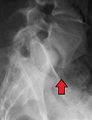

MRI of L5-S1 spondylolisthesis- X-ray of a grade 4 spondylolisthesis at L5-S1 with spinal misalignment indicated

Spondylolisthesis L5/S1